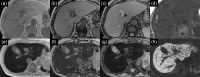

MRI is widely used in clinical practice for detecting liver diseases. Since the introduction of gadoxetic acid, MRI has become the most effective modality for the detection and characterization of focal liver lesions. According to previous meta-analyses, the area under the receiver operating characteristic curve (AUROC) was 0.97-0.99 for the diagnosis of small hepatocellular carcinoma (≥ 2 cm) by gadoxetic-acid-enhanced MRI. Moreover, the AUROC for the diagnosis of colorectal liver metastases was significantly high (0.98). Despite gadoxetic acid's drawbacks, its clinical utility outweighs them, making it the contrast agent of choice in routine liver MRIs. Moreover, clinically, liver MRI has become more prevalent for a quantitative assessment. Liver fibrosis can be evaluated using MR elastography; whereas, hepatic steatosis and iron overload can be evaluated using proton density fat fraction, with high accuracy and reproducibility. This article reviewed the usefulness of liver MRI, which can be a comprehensive imaging modality in clinical practice.